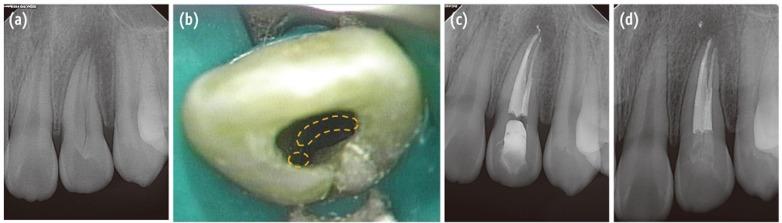

Maxillary lateral incisors usually exhibit a single root with a single canal. However, maxillary lateral incisor teeth with unusual morphology of root canal system are frequently reported. These cases of variable root canal anatomy can be treated well by nonsurgical endodontic methods. A detailed description of root canal morphology is fundamental for successful endodontic treatment. Treatment using an operating microscope, radiographs from different angles, and cone-beam computerized tomography (CBCT) can produce more predictable endodontic outcomes.

上颌侧切牙通常有一个牙根和一个根管。然而,根管系统形态异常的上颌侧切牙屡有报道。这些根管解剖结构各异的病例可通过非手术根管治疗方法得到良好治疗。详细描述根管形态是根管治疗成功的基础。使用手术显微镜、不同角度的X光片以及锥形束计算机断层扫描(CBCT)进行治疗可产生更可预测的根管治疗效果。